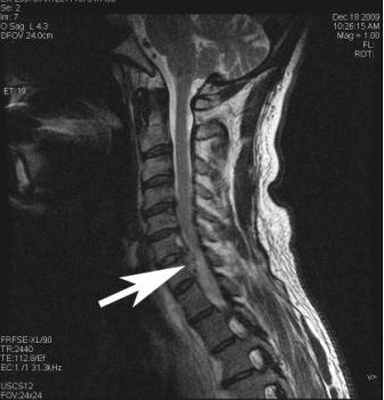

(Слева) Аксиальный срез, Т1-ВИ, пациента, которому ранее выполнялся задний межтеловой спондилодез (PLIF): дуральный мешок окружен широкой зоной низкой интенсивности сигнала, представляющей собой перидуральный фиброз. В области межтелового пространства определяется артефакт, связанный с установленным сюда межтеловым кейджем.

(Справа) На аксиальном Т1-ВИ с КУ у этого же пациента отмечается диффузное контрастное усиление зоны эпидурального фиброза, вызывающего минимальную деформацию дурального мешка. В толще фиброзных тканей замурованы выходящие на этом уровне корешки спинного мозга.